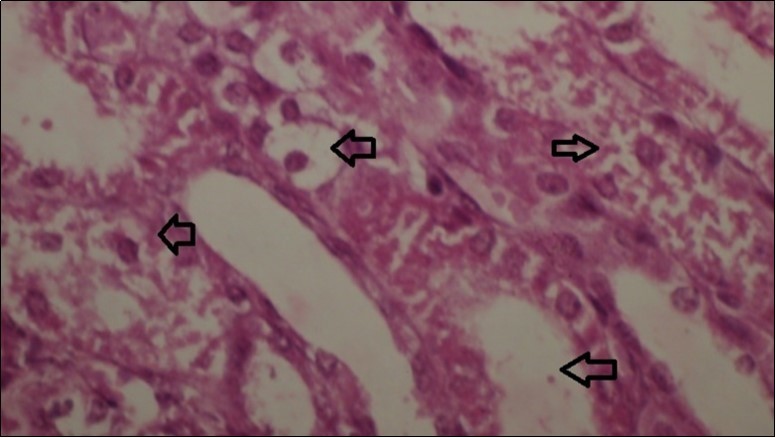

Figures 6.kidneys (dead cattle less than 1 year old) showed severe hydropic degeneration of renal tubular epithelium accompanied by dilated renal tubules, vesicles formations and casts (arrows). (H&E, X 100)

Figures 7.kidneys (dead cattle less than 1 year old) showed severe hydropic degeneration of renal tubular epithelium accompanied by dilated renal tubules, vesicles formations and casts (arrows). (H&E, X 60)